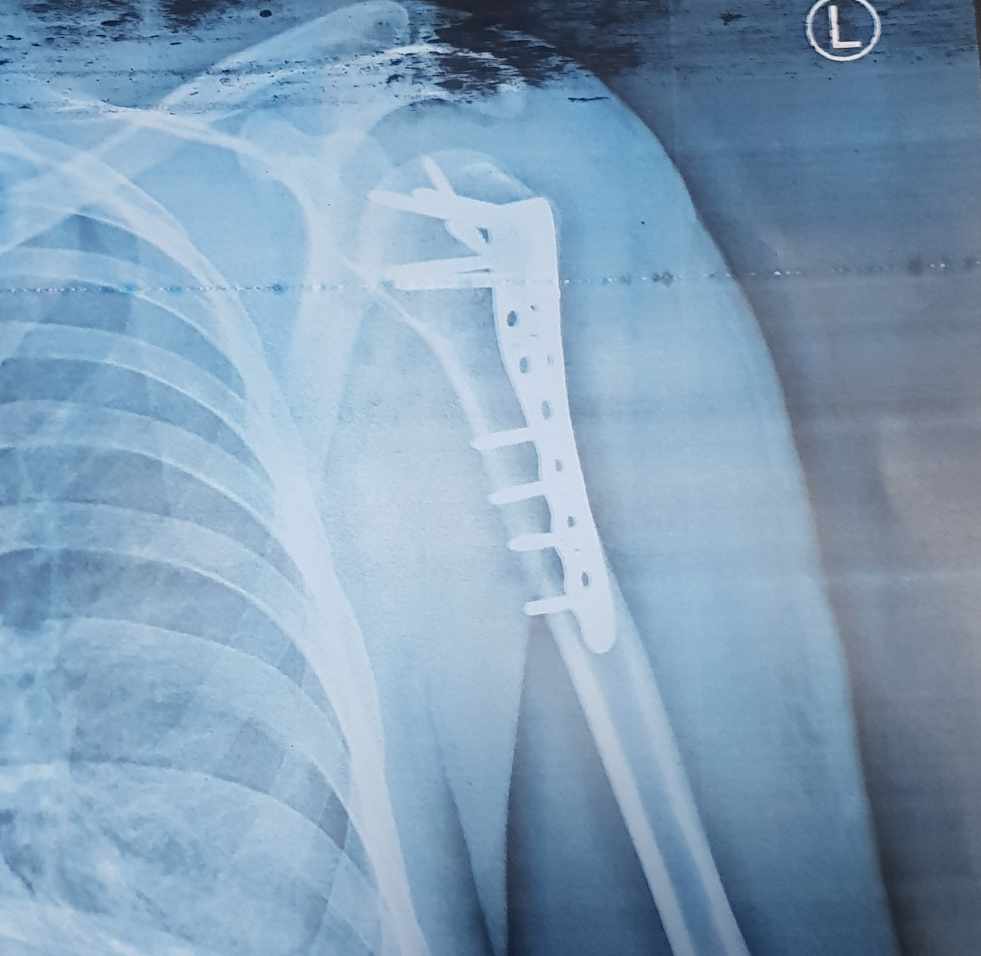

نمونه کارها

جراح و متخصص ارتوپدی